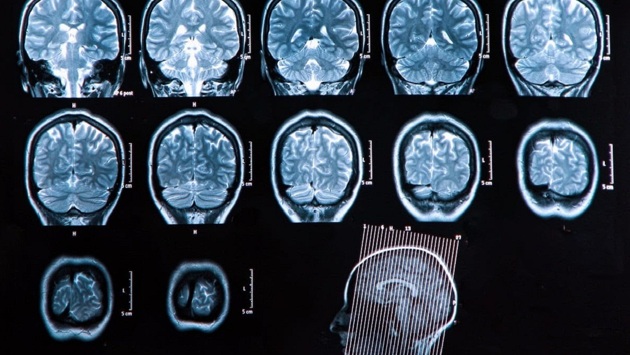

Последние исследования по изучению побочных действий препаратов от болезни Альцгеймера показали, что некоторые из них могут нанести вред здоровью.

К таким относятся препараты, которые ранее называли эволюционными, леканемаба и донанемаба. Первый препарат совместно разработали японская компания Eisai и ее американский партнер Biogen. Донанемаба была разработана американской компанией Lilly.

Как оказалось, они могут привести к уменьшению объемов мозга, а также кровотечениям, сообщает The Times.

Правда, исследования показали, что они могут очистить мозг от токсичного белка амилоида, который считается отличительным признаком болезни Альцгеймера.